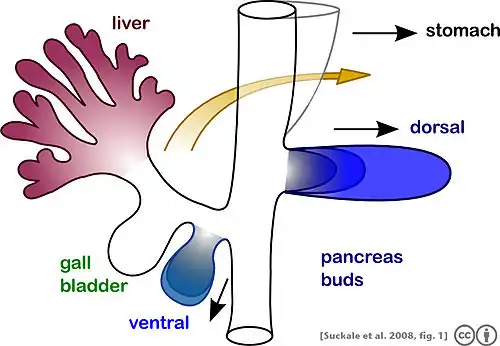

| Embryonic development of pancreas. Showing the dorsal rotation and fusion of ventral bud with dorsal bud during the sixth and seventh week of gestation. |

The pancreas is responsible for secreting various enzymes for most digestion. It is a retroperitoneal organ posterior to the great curvature of the stomach. Its anterior surface is covered by the parietal peritoneum while the posterior surface contacts the aorta as well as other viscera on the left posterior body wall. Its 15 cm entity is divided into three parts, a globular head attached to the right side of duodenum, a long body, and a blunt head.[14] In embryonic development, the pancreas is formed by the convergence of the two pancreatic buds (dorsal and ventral) during the sixth and seventh week of gestation, but the development of these two buds is initiated at about week 4.[14] During the gestation phase which takes place at week 4, the dorsal bud develops from the dorsal mesentery, and form the body and tail of the pancreas. Meanwhile, the ventral bud arises inferior to form the head of the pancreas.[1] Two weeks later, the ventral bud will rotate dorsally and fuse with the dorsal bud to form the pancreas. The fusion of the duct happened at the same time, to form the duct of Wirsung and the duct of Santorini.[15] Any deviation from the normal pancreatic embryogenesis process can potentially leads to congenital malformation of the pancreas. Among all anomalies, Pancreatic Divisum is the most prevalent one, followed by Pancreatic Heterotopia.[1][7] In comparison, a complete agenesis of dorsal pancreas is rare and often associated with infant mortality.[1]